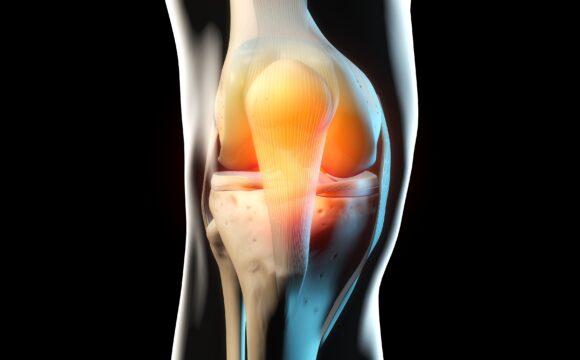

- Rupturi de ligamente și tendoane

- Leziuni sportive